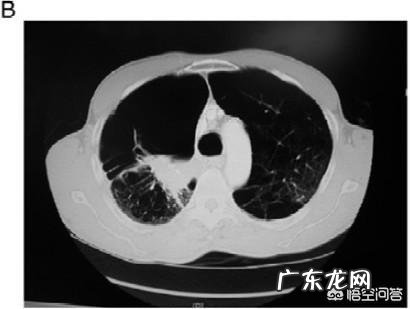

文章插图